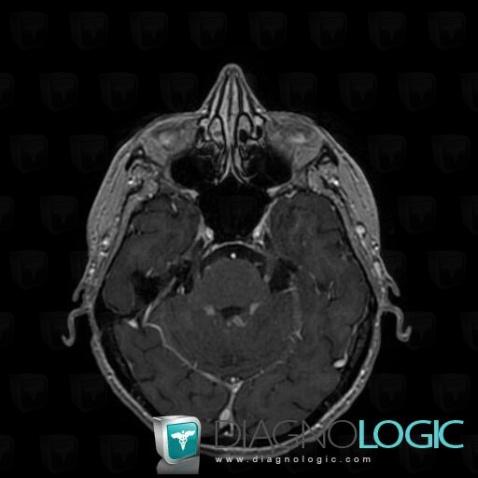

Les images ci-dessous illustrent ce dossier pour les diagnostics Carcinose méningée, Méningite carcinomateuse, pour les modalités (IRM)

Voici les informations spécifiques à l'image clé ci dessus:

- Diagnostic Méningite carcinomateuse, Localisation(s) Région cortico sous corticale, comportant les gammes Lésion sous corticale

Voici les informations spécifiques à l'image clé ci dessus:

- Diagnostic Méningite carcinomateuse, Localisation(s) Région cortico sous corticale, comportant les gammes Lésion corticale